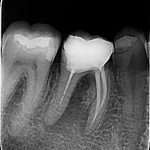

• Intraoralne RVG snimke: Za detaljnu dijagnostiku pojedinačnih zuba, idealne za otkrivanje karijesa ili problema s korijenom.

Intraoralne RVG snimke

Intraoralna RVG snimka zuba, jako se često radi kad je riječ o popravku jednog zuba.Vrlo je praktična jer se na njoj vide tri ili četiri zuba.